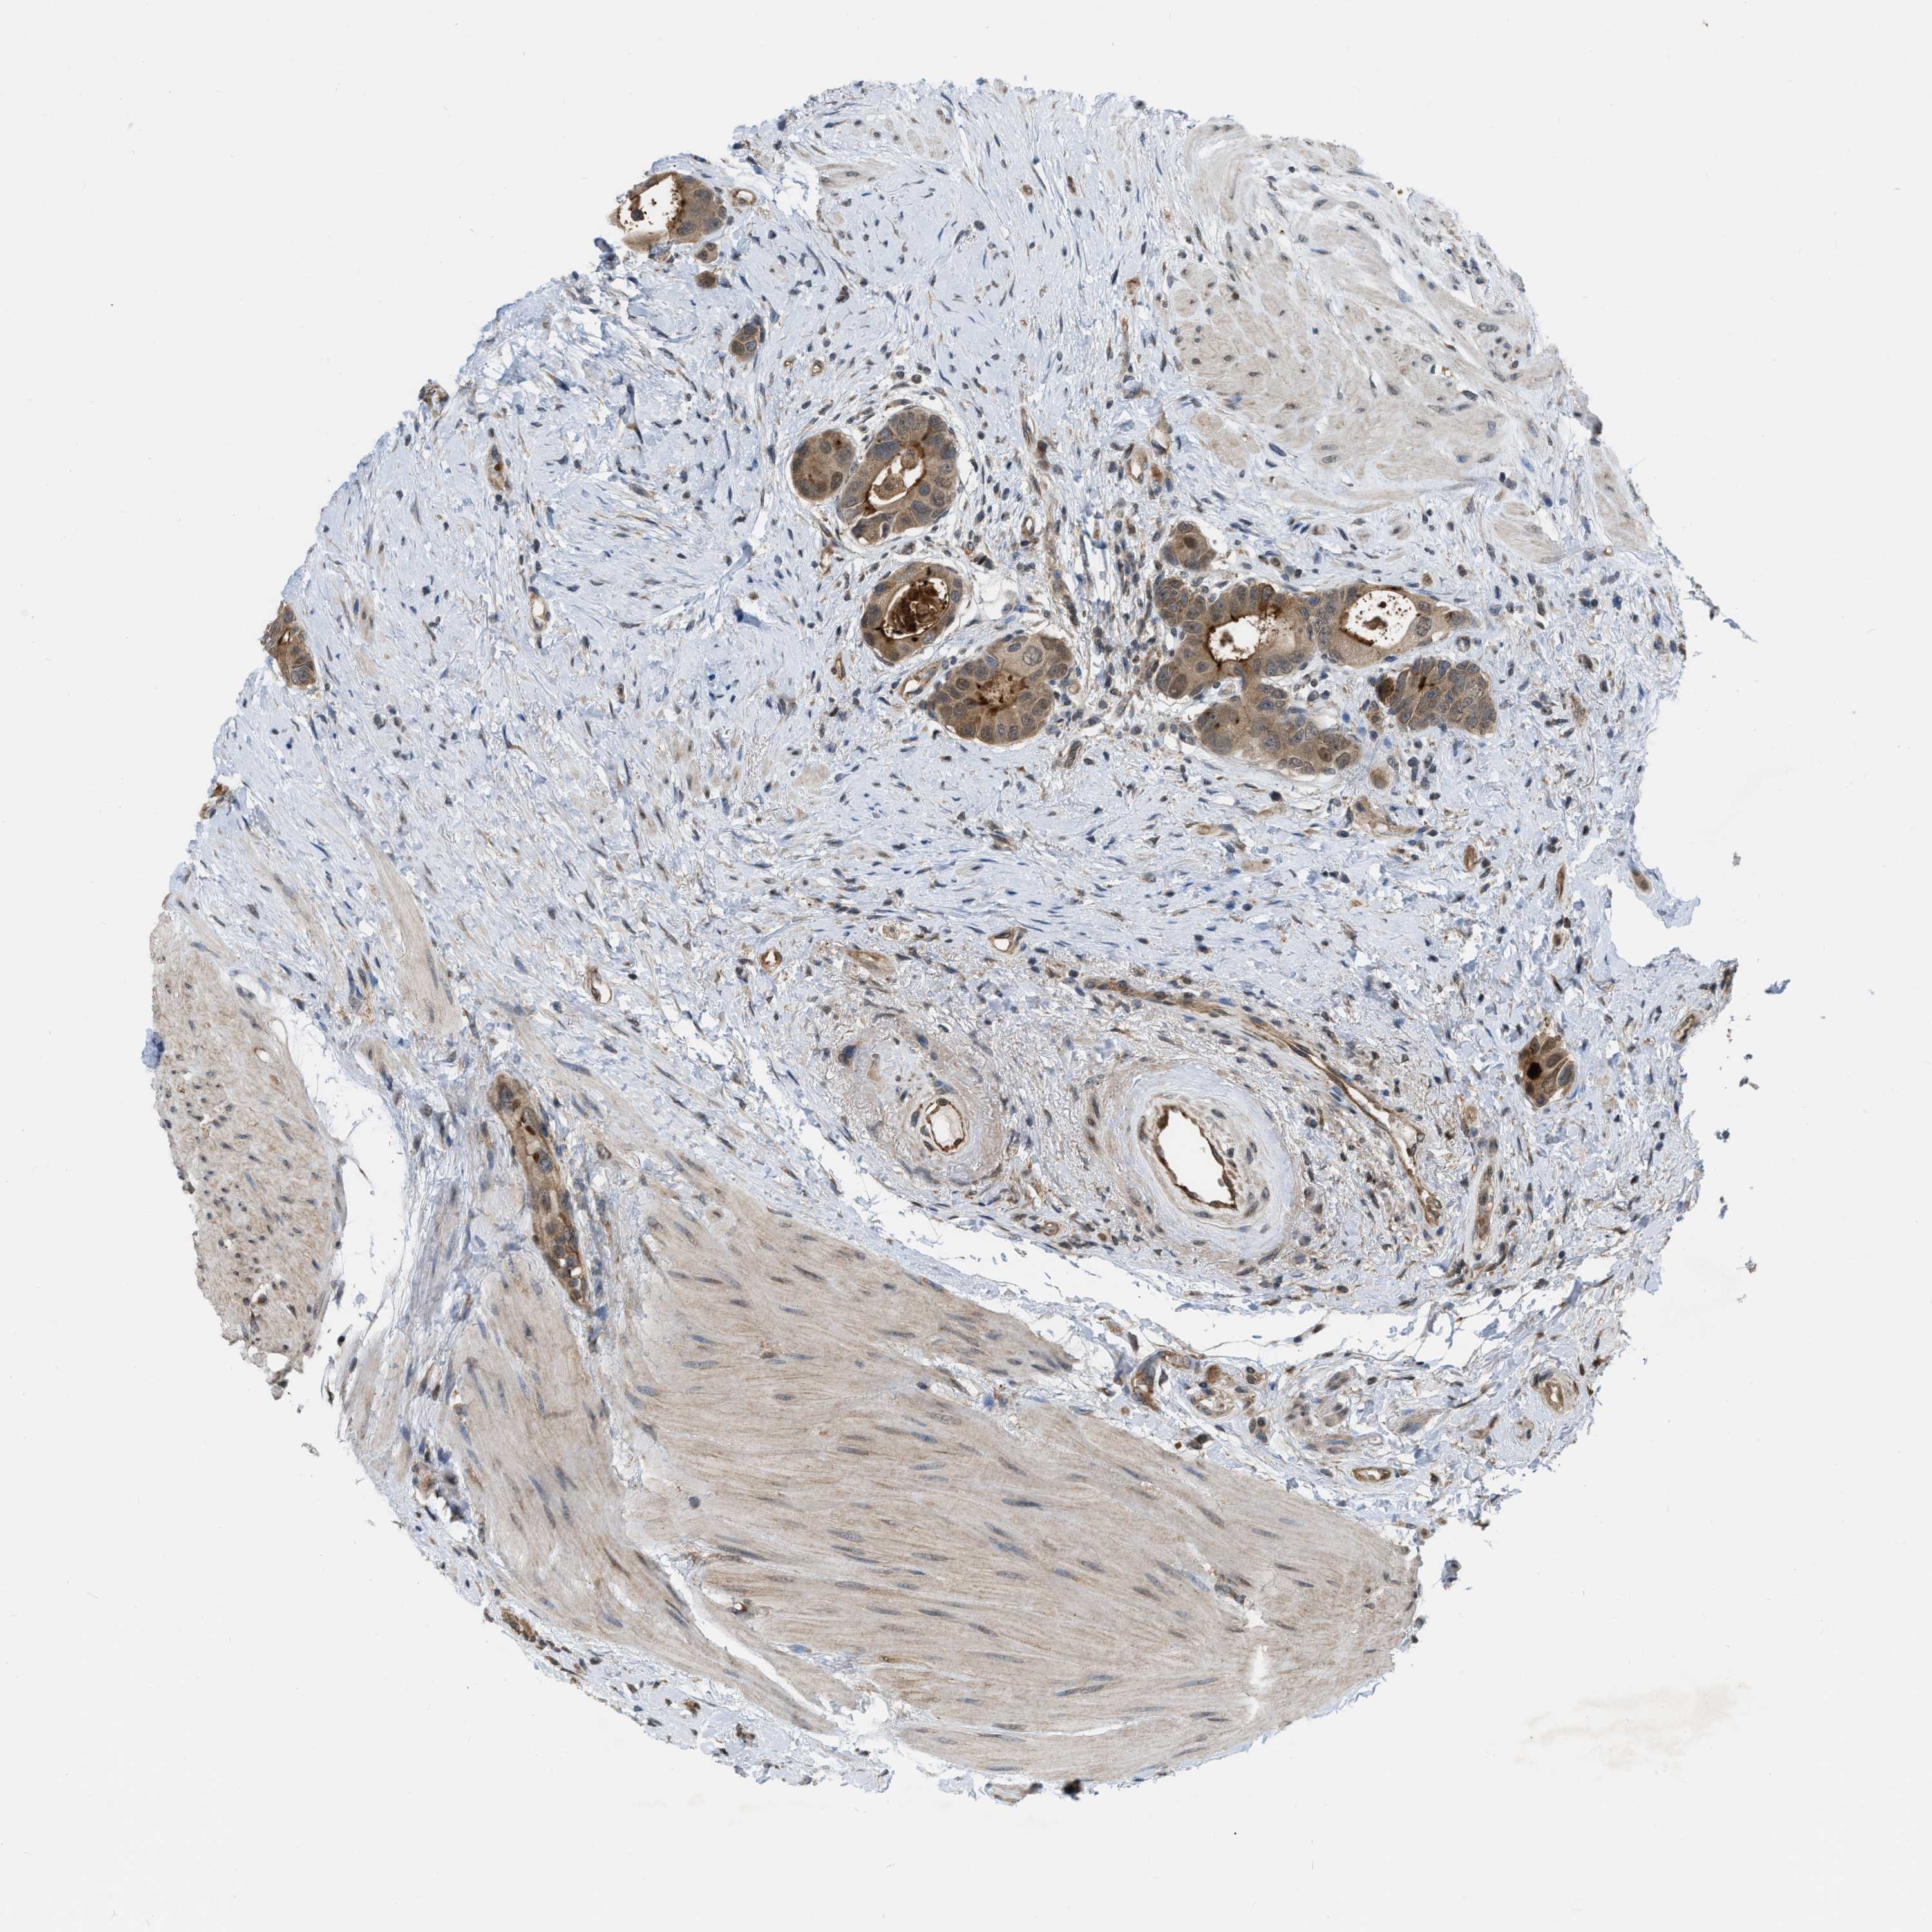

CANCER COLORECTAL CANCER Show tissue menu

Colorectal cancer

Human cancer

Colon adenocarcinoma

Rectum adenocarcinoma